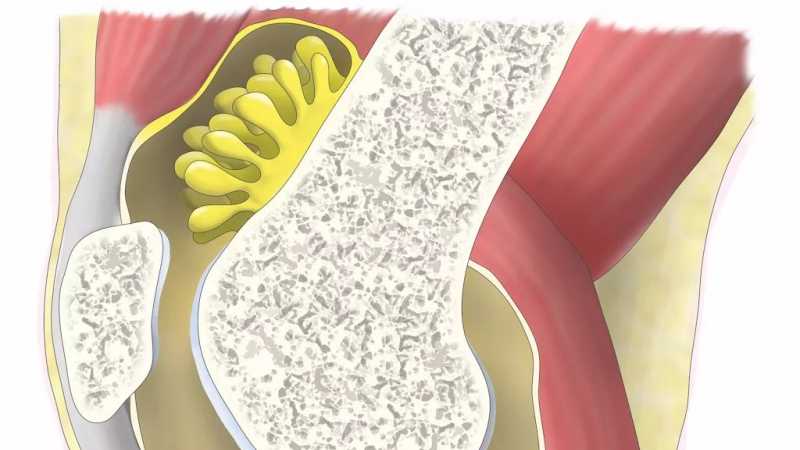

膝关节滑膜解剖

膝关节滑膜是覆盖于关节囊内面并构成关节囊内层的一层薄膜,具有分泌滑液、润滑关节、营养关节软骨等功能。在膝关节内,滑膜覆盖交叉韧带、腘肌腱以及半月板之下的冠状隐窝等结构,同时,髌韧带内面也有滑膜覆盖。关节软骨和半月板处无滑膜。滑膜内含有丰富的血管和神经,对关节的生理功能和病理变化起着重要作用。

正常滑膜,影像不能显示。滑膜增厚,伴有关节腔积液时,可显示滑膜。增强扫描可直接显示增厚的滑膜。